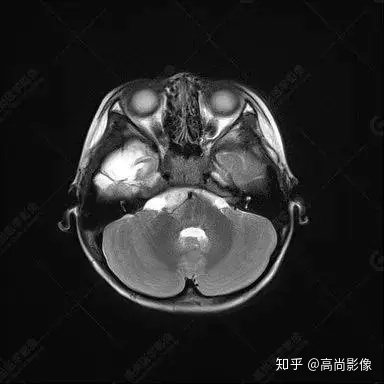

右側(cè)顳葉腫瘤切除術(shù)后(具體不詳):右側(cè)顳部骨質(zhì)不連續(xù)呈術(shù)后改變,右側(cè)顳葉術(shù)區(qū)見片狀長(zhǎng)T1長(zhǎng)T2信號(hào)影,F(xiàn)LAIR呈低信號(hào);術(shù)區(qū)后方右側(cè)顳枕葉見一巨大占位性病變影,邊界欠清,大小約6.2×5.8×4.3cm(前后×左右×上下),信號(hào)不均勻,T1WI呈等稍低信號(hào)間雜少許高信號(hào),T2WI呈高稍低混雜信號(hào),DWI示部分病灶彌散受限,相應(yīng)ADC圖減低,磁敏感序列見部分呈極低信號(hào),增強(qiáng)掃描可見明顯不均勻強(qiáng)化,鄰近硬腦膜及小腦幕增厚并明顯強(qiáng)化;另延髓右前方及右側(cè)橋小腦角區(qū)見一不規(guī)則形異常信號(hào)影,大小約3.2×1.3×3.7cm(左右×前后×上下),呈長(zhǎng)T1稍長(zhǎng)T2信號(hào),F(xiàn)LAIR呈等信號(hào),DWI未見受限,增強(qiáng)后明顯均勻強(qiáng)化,鄰近腦膜明顯強(qiáng)化。鄰近腦實(shí)質(zhì)及右側(cè)顳角明顯受壓;左側(cè)大腦半球未見局灶性信號(hào)異常,中線結(jié)構(gòu)稍左移。

右側(cè)顳葉腫瘤切除術(shù)后:現(xiàn)術(shù)區(qū)后方右側(cè)顳枕葉及延髓右前方占位,右側(cè)顳枕部硬腦膜及小腦幕明顯強(qiáng)化,結(jié)合既往影像資料,考慮為胚胎源性惡性腫瘤,如非典型畸胎樣/橫紋肌樣瘤(AT/RT)或原始神經(jīng)外胚層腫瘤(PNET)。